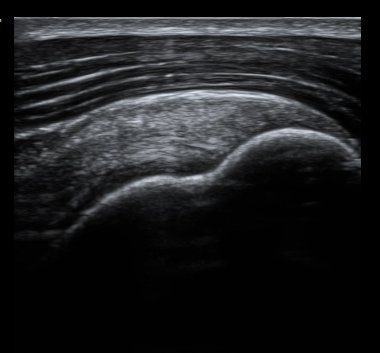

±Ø»ó°Ç Á¾´Ü¸é°Ë»ç¿Í Ⱦ´Ü¸é°Ë»ç¿¡¼­ ±Ø»ó°Ç³» ¹Ì¼¼ÇÑ °£±ØÀÌ °üÂûµÊ(±×¸² 6, 7, 8).

°ßºÀ ¿ÜÃø¿¡ ŽÃËÀÚ¸¦ ´ë°í ½ÃÇàÇÑ Ãæµ¹°Ë»ç¿¡¼­ °ßºÀ ¿ÜÃø¿¡ ¼ö¾×Àú·ù°¡ °üÂûµÇ¾ú´Ù.(±×¸² 9).